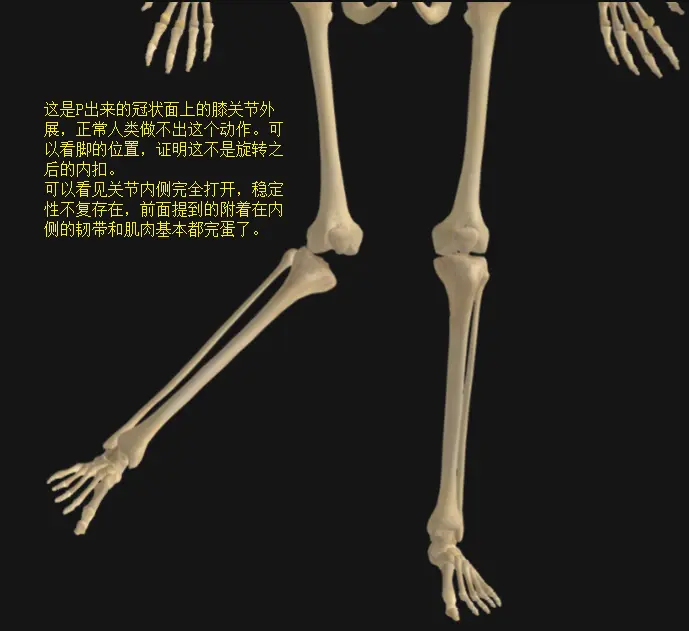

上述所有肌肉韧带的特点都是不具备膝关节左右活动,即外展内收功能的,膝关节周围的肌肉只有屈伸功能,以及“在屈膝位上,很少量的旋转功能”。它所有的构造(骨,软骨,韧带,肌肉,软组织等…)从上到下从内到外都是为了屈伸功能和承重服务的,这些解剖结构决定了在实际使用场景中,膝关节运动要避免旋转和左右两侧活动的力。

了解了膝关节的结构之后我们可以知道,膝关节的稳定性是由关节周围的肌肉韧带来完成的,在前后的屈伸过程中伸膝肌和屈膝肌可以控制动态稳定,而膝关节不存在外展内收功能,所以无法对膝关节左右方向上的稳定进行动态控制。如果出现了类似左右方向上的力,维持膝关节左右方向的静态稳定的任务会落到周围韧带上,于是韧带压力过大,这是我们不希望出现的事。

下肢在动作中是一个整体,这个观念很重要!由解剖结构限制我们无法在膝关节控制左右方向,但因为下肢是一个整体,我们可以通过髋关节来控制股骨,通过踝关节控制胫骨,以此来维持两根骨在膝关节上的正确位置,现在观点正式表达出来就是:“膝关节的损伤不是因为膝关节的结构不够强壮,而是相邻的髋关节和踝关节对下肢的控制不够稳定,于是膝关节(股骨下端和胫骨上端)的对位或者受力出现异常。膝关节不是灵活关节,所以在下肢运动中膝关节损伤优先出现。”

膝盖的运动轨迹应该在力线上才能获得更安全高效的抗重力性能,不过前面我们提到了膝关节并没有控制自己左右移动的能力,于是要看向髋关节控制的股骨和踝关节控制的胫骨。先从髋关节开始看起,髋关节的外展肌内收肌和内旋肌外旋肌的稳定和相互拮抗,才能为髋关节的屈伸功能提供稳定的固定。股骨或者胫骨的角度或位置变化会影响膝关节的对位,改变原本均衡的受力,这时候下肢力线就歪了。

股骨内旋之后,强迫脚尖朝前走路,这时候小腿是要相对大腿做外旋,膝关节会受到方向相反的剪力,膝关节也偏离了下肢力线,这时膝关节外侧的压力会增加,内侧肌肉韧带被拉长。

股骨外旋之后,强迫脚尖朝前走路,则小腿相对大腿会做出内旋,这时膝关节向外偏离力线,关节内侧压力增加,外侧肌肉韧带被拉长。

为什么骑车都能骑到半月板损伤?左摇右摆的膝关节轨迹带来歪斜的力线,每一次屈伸都是对周围肌肉韧带进行拉扯,对夹在中间的半月板进行蹂躏,对骨关节面的挤压,高踏频是精细研磨,高齿比是暴力撕扯。

当然也不是每次都是半月板先倒霉,下肢力线的歪斜更多的拉扯周围负责限制的肌肉和韧带,因之肌肉可以拉长也可以紧张,韧带可以撕裂也可以断裂……

髌骨的上下滑动也会受影响,因为髌骨是通过髌腱附着在胫骨粗隆上的,而滑动的凹槽却在股骨的股骨滑车上,于是大小腿的对位不正还会影响髌骨滑动轨迹增加髌骨软骨压力甚至脱位和半脱位…情况太多就不一一列举了,力线歪斜可以说是万恶之源。